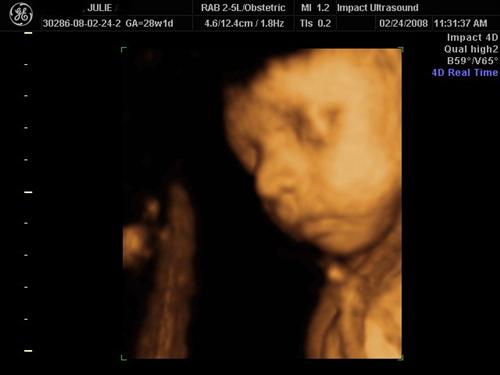

3D SONO PICS

Here is my He looks just like his daddy!

Awesome pics! He really does look like Ray. I remember seeing the pictures of Ray as a kid when you guys were getting married, and that is definitely who that baby looks like!

Here is Ray's baby picture... they look like twins to me! Image Attachment(s):

oh WOW - he looks JUST LIKE Ray & Mike!!!